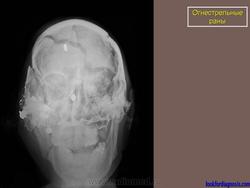

Огнестрельные раны.

Огнестрел и военные действия.

1.pulya_.29.i.slayd28.jpg2yupulya.30.i.slayd29.jpg3.pulya_.32.i.slayd31.jpg4.pulya_.33.i.slayd32.jpg